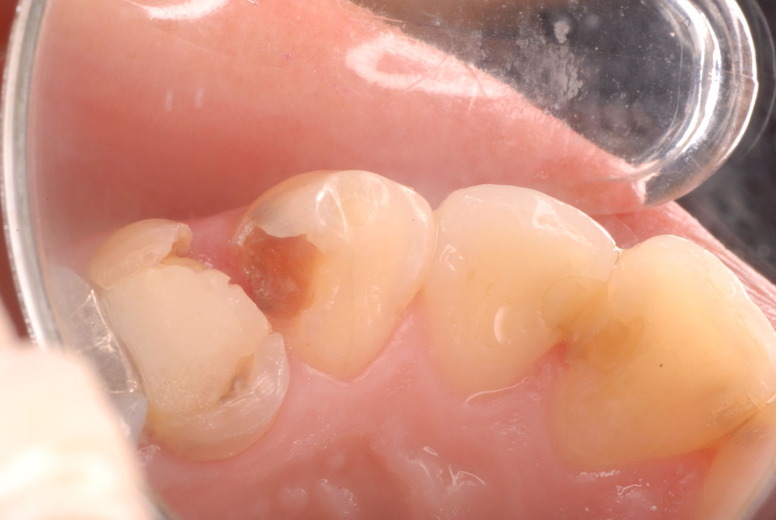

ご自分でやられても歯茎から血が出ないと話をされていましたが、私がブラシを当てると悲惨な状態であることがわかりました。

何故歯が悪くなるのか、歯周病で抜けるのか分からなければ何を入れても歯は悪くなり抜けていくのです。

病気を治しましょう。それから差し歯や入れ歯を入れましょう!物を入れれば入れるほど、磨き方や掃除の仕方が上手にならなければ、すぐ抜けてくるのです。